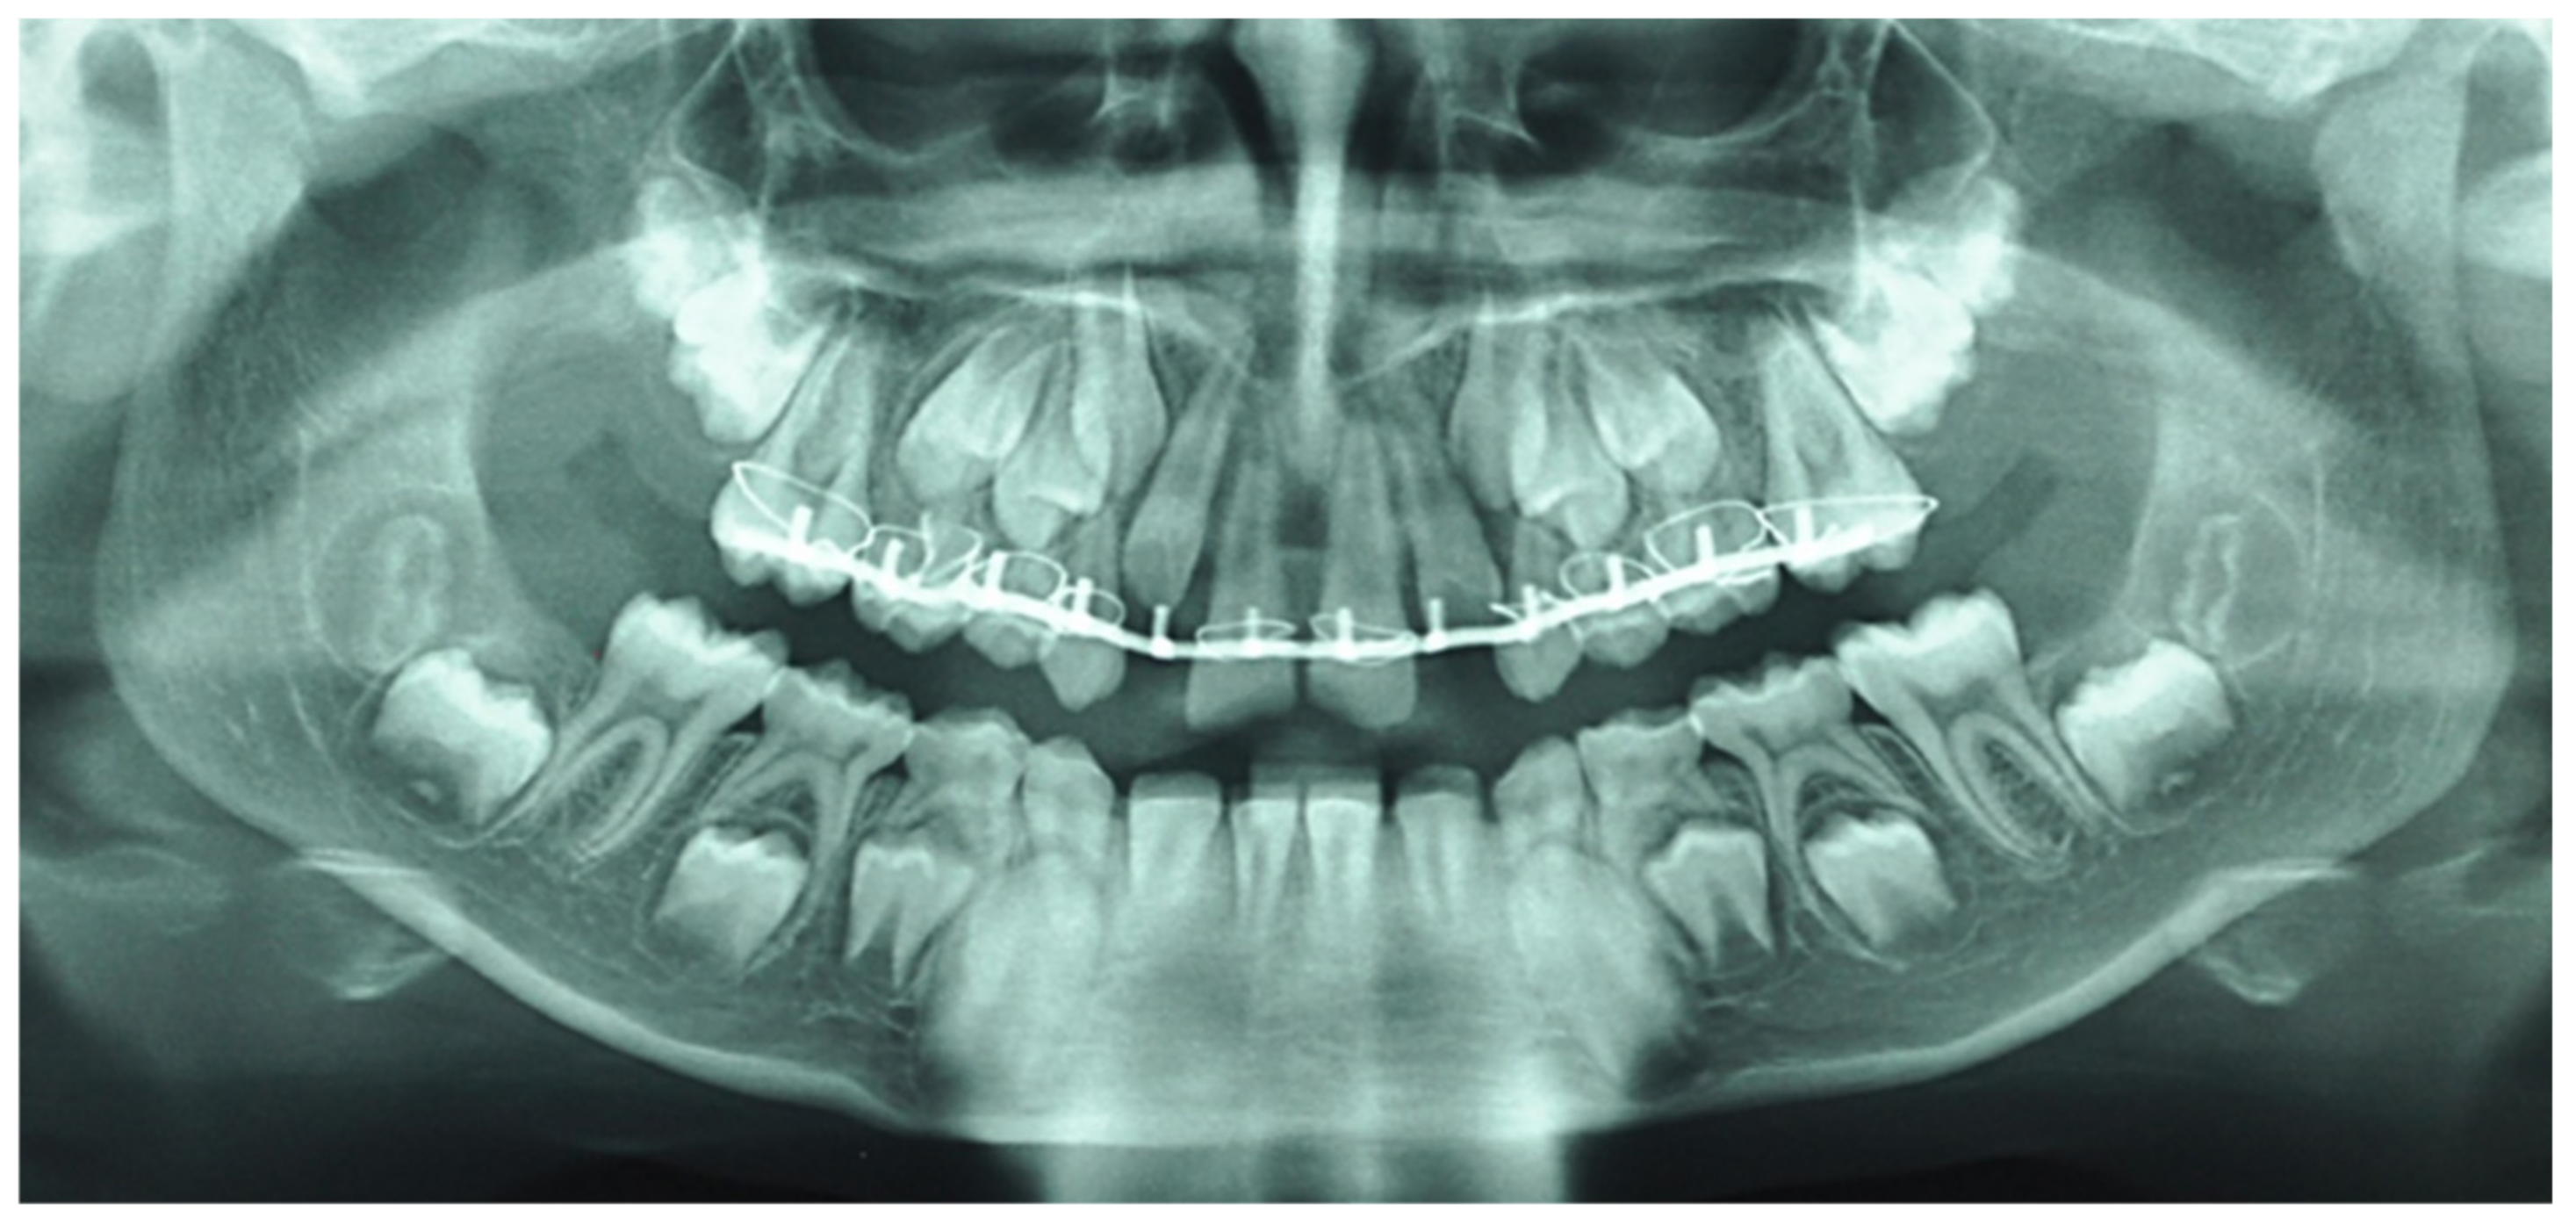

| August 2015: Maxilla-facial trauma, Dental traumatology, Alveolar fracture | Intrusive luxation | Complete extrusive luxation | Intrusive luxation | |

| August 2015: General Anesthesia | Reducing of extrusive luxations | |||

| Dautrey arch placed with inter-dental fixation using 2.0 steel wire between both first upper molar teeth to allow reduction in the associated alveolar fracture | ||||

| October 2015: Orthodontics consultation | Severe mobility and root resorption | |||

| Removal of the Dautrey arch and replacement with a fixed multi-fastener maxillary appliance | ||||

| December 2015 (Dentist treatment) | Endodontic treatment with calcium hydroxide and Gutta Percha | |||

| April 2018 | “pink spot” lesions/invasive cervical resorption of class III according to Heithersay classification [15,16]/negative response to vitality test | Slight mobility/complete root inflammatory resorption around the gutta percha filling | “pink spot” lesions/invasive cervical resorption of class II according to Heithersay classification [15,16]/negative response to vitality test | |

| Figure 3, Figure 4 and Figure 5 | ||||